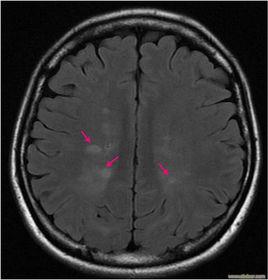

腦脊髓液(cerebrospinal fluid ) 由占據脊椎動物腦室壁一部分的脈絡叢(圓口類以上有之)分泌的液體,充滿腦室。從第四腦室的菱腦正中孔與菱腦外側孔達蛛網膜下腔,向下到脊髓周圍。除參與機械的保護作用之外,也成為中樞神經系統代謝產物的排出通路,最後被靜脈系統所吸收。是弱鹼性透明的水樣液,一毫升中含1—6個淋巴球。